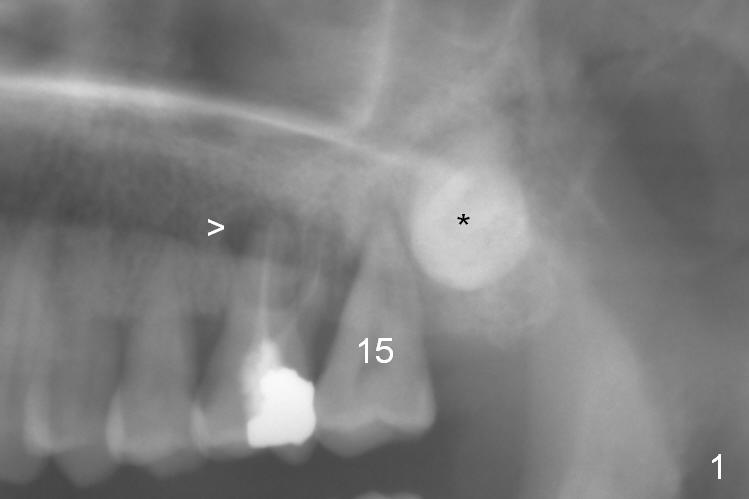

A 51-year-old lady (ZC) requests #15 extraction and immediate implant (Fig.1,2). The affected tooth is between periapical radiolucency of #14 (Fig.1 >) and the impacted 3rd molar (*). Discuss the possibility of extracting #14 and 16 at the same time. After extraction (Fig.3), osteotomy is initiated on the mesial slope of the socket (treated with Clindamycin, Fig.4). Once the cortex is penetrated, the trajectory is changed (Fig.5). After withdrawing the pilot drill, insert a parallel pin for X-ray. Adjust osteotomy position and angulation and finish placing an implant (Fig.6).